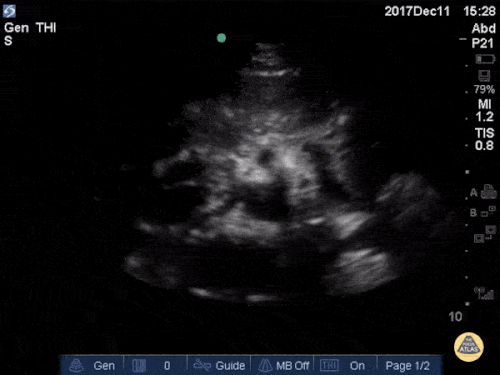

Aorta - Seagull Sign

The vertebrae, seen here as the deepest structure as a hyperechoic arch with posterior shadowing (horseshoe sign), is a key anatomic reference when scanning the aorta. The aorta is located immediately anterior to the vertebrae and to the right side on the screen (patient’s left). Contrast this with the inferior vena cava, which is seen to the left of the aorta, often in an oval or teardrop shape. In the center of the screen we see the celiac trunk branching off the proximal abdominal aorta. The Y-shaped “seagull sign” is created by the celiac trunk as it branches into the hepatic artery (left) and splenic artery (right). The portal venous confluence is visible between the IVC and the hepatic artery.